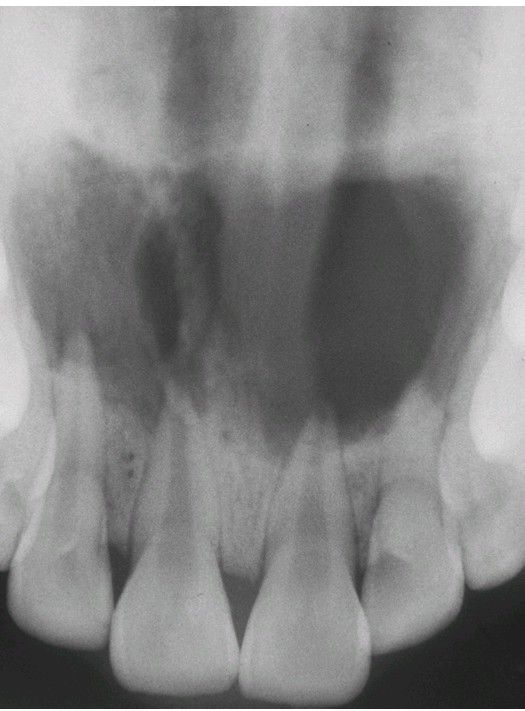

Periapical Abscess

Multiple, overlapping radiolucencies of the anterior maxilla are present. All four maxillary incisors exhibit pulpal necrosis